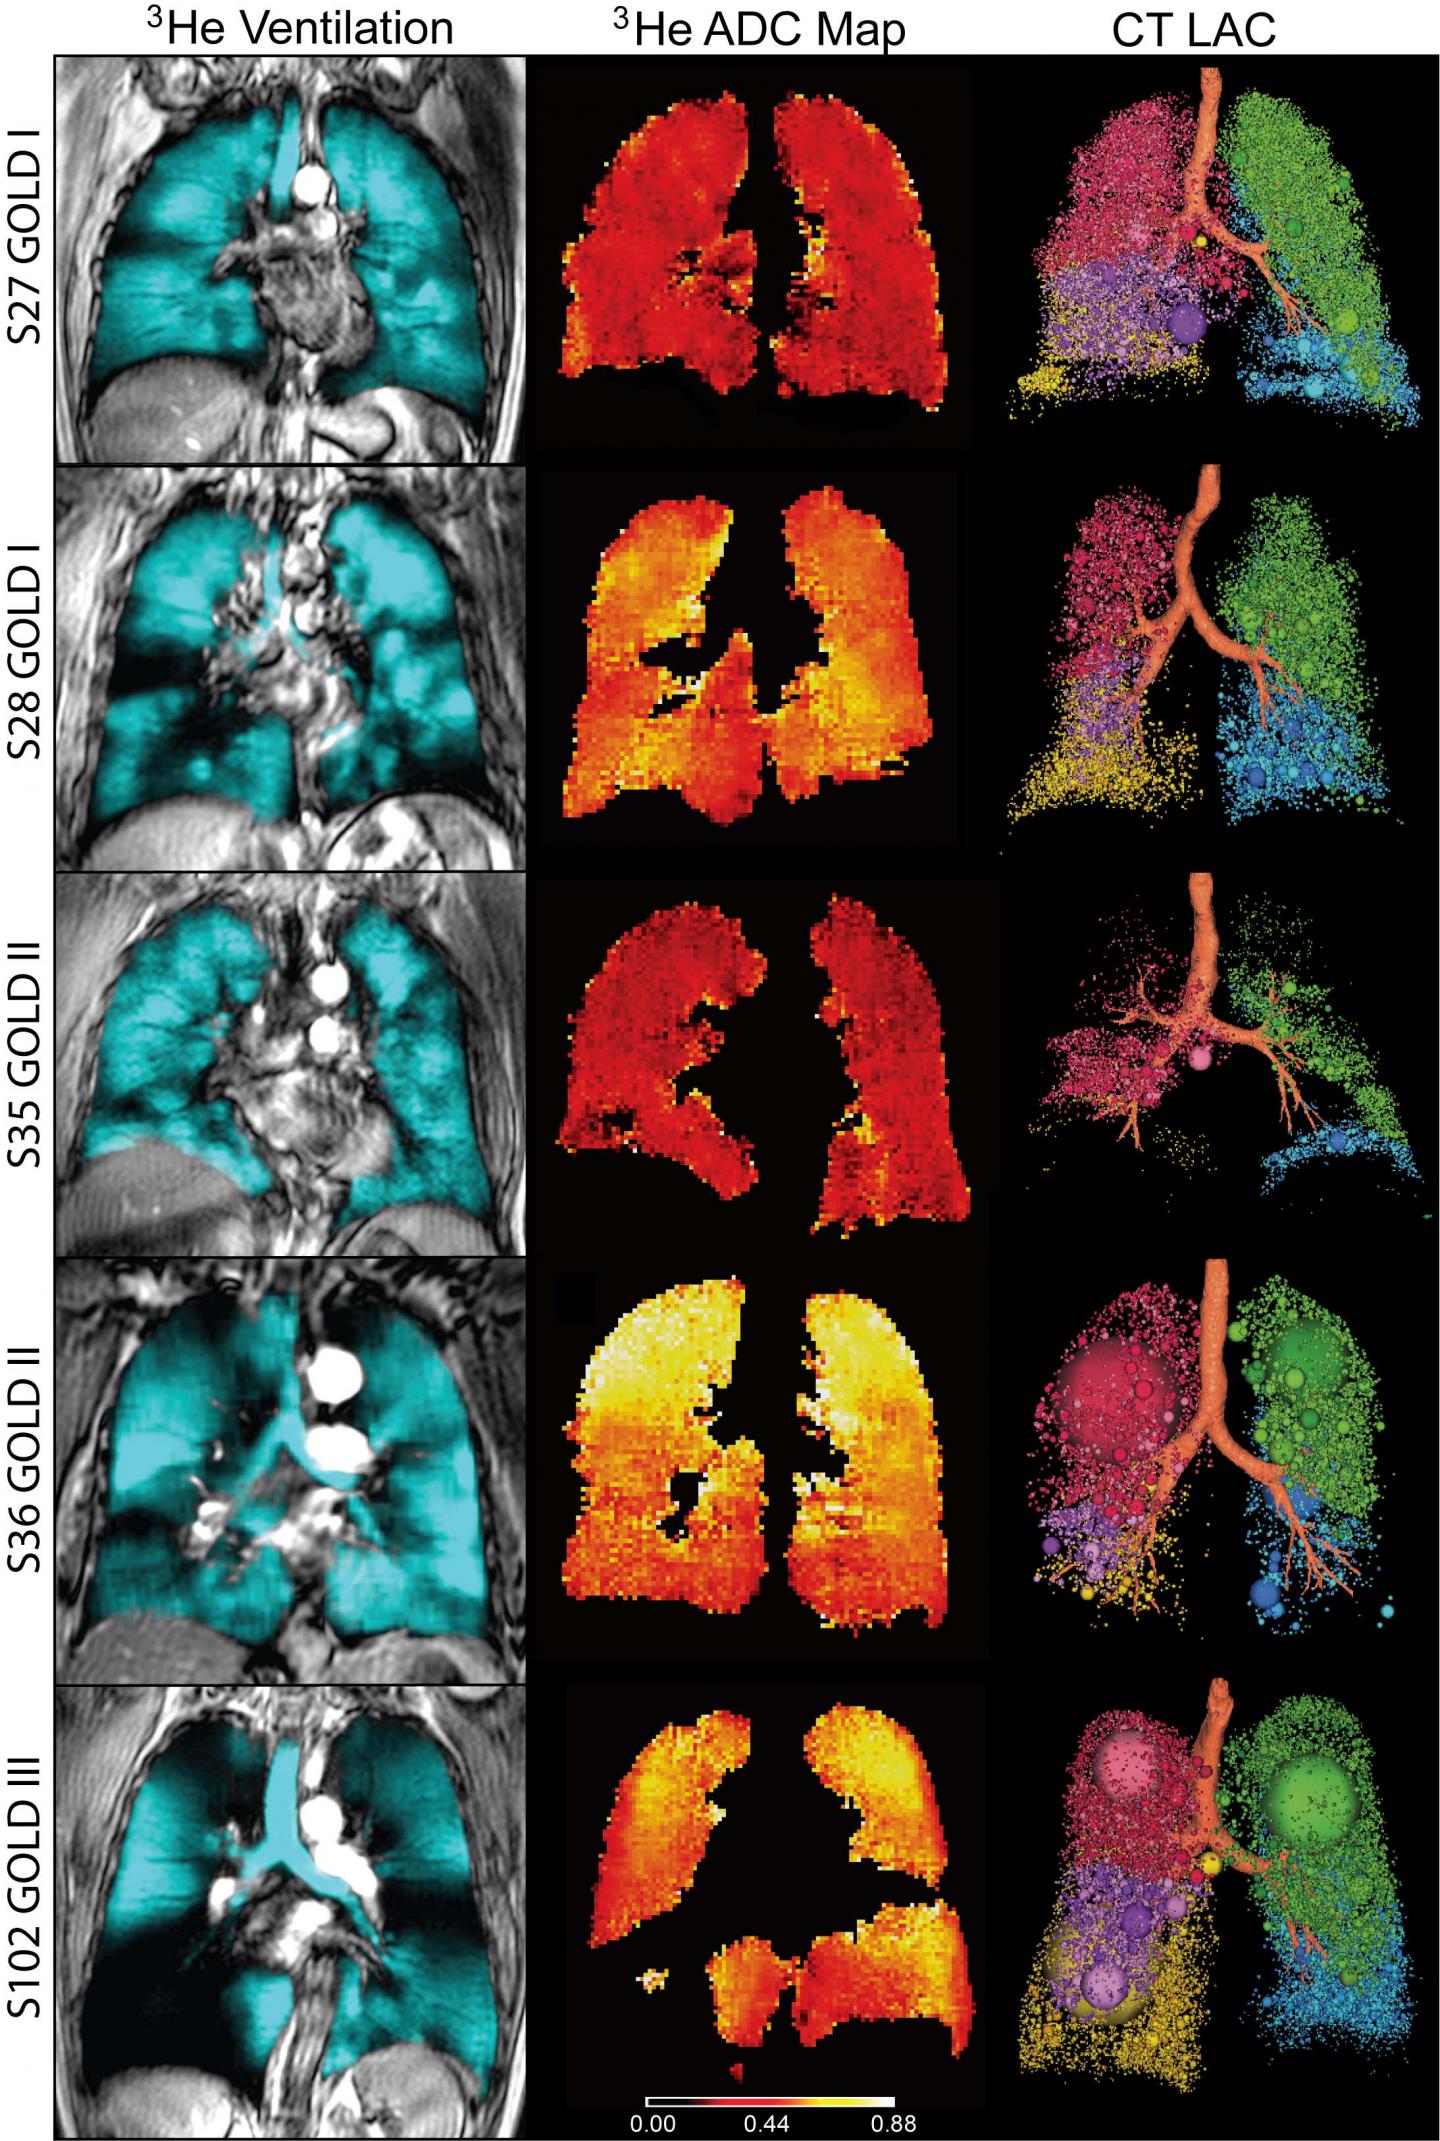

For the study, they performed conventional CT and inhaled noble gas MRI, a technique for visualizing air spaces in the lungs, on 116 people with COPD, including 80 with milder disease. The patients also underwent lung capacity testing, filled out a quality of life questionnaire and took a six-minute walk to measure their exercise tolerance over a short period of time.

The results showed that in mild-to-moderate COPD patients with modestly abnormal FEV1, MRI measurements of emphysema were strongly correlated with exercise limitation, while both CT and MRI measurements of emphysema helped explain symptoms.